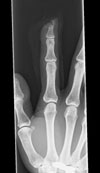

右人差し指が事故で

第一関節が潰れて抜けてしまった

骨まで潰れて

潰れて汚れきった第一関節を

綺麗に洗浄して

縫い合わせてくれたので

指を詰めた状態でなく

かろうじて第一関節が

繋がっている感じでした。